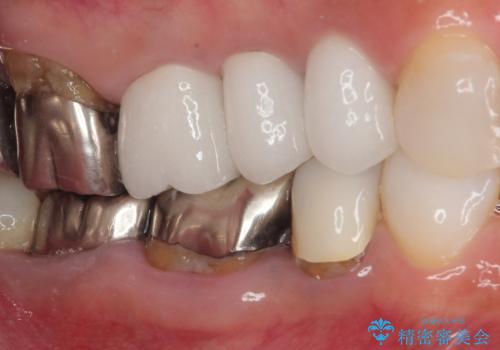

奥の銀歯の幅が大きかったこともあり、細長いクラウンの見た目は大きく改善することができました。

今後は他の銀歯の治療を進めていく計画です。